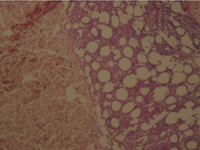

The histologic sections of [patient (a), taken by punch biopsy (4mm) from right thigh] revealed superficial and deep, intense plasma cellular and lymphocytic infiltrate, primarily in the lower dermis and fat septae with spillover to the fat lobules. Fibrosis was present in the deep dermis and in the fat. There was no vasculitis. (Fig 7,8).